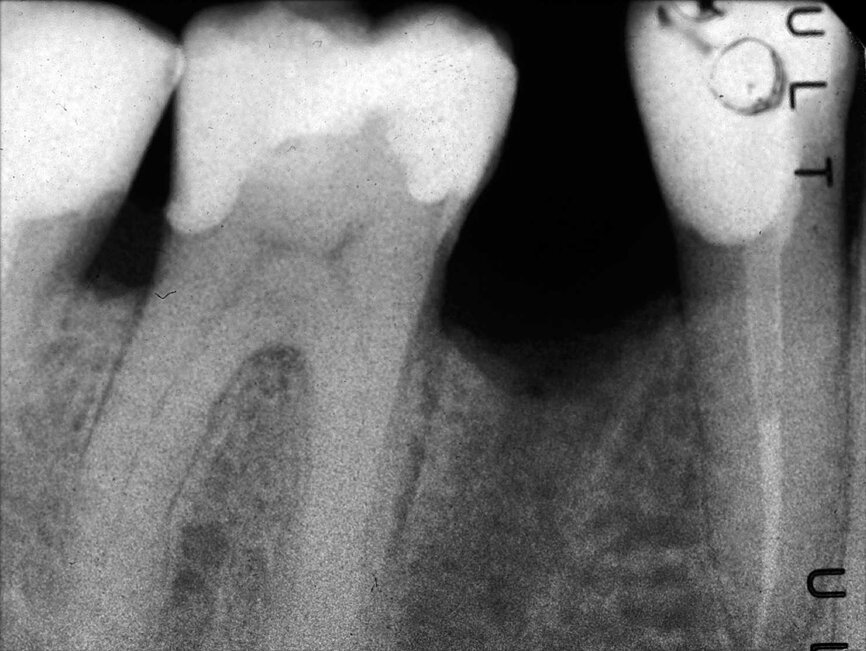

Dans la prémolaire maxillaire présentée dans les figures 5 et 6, le fistulogramme indique la présence d’une lésion apicale, qui s’étend en direction coronaire jusqu’au tiers moyen de la racine. La décision clinique pourrait donc s’orienter vers un retraitement orthograde ; toutefois, le cliché CBCT nous donne une tout autre vision de la situation que celle de la radiographie, dans la mesure où il montre une lésion irréversible de la dent due à un traitement antérieur, et la nécessité de l’extraire.